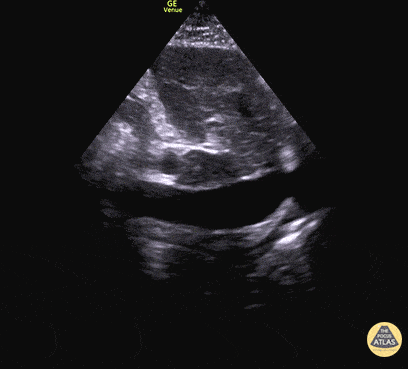

Based on the ultrasound image, which shock etiology is most likely?

1 pts